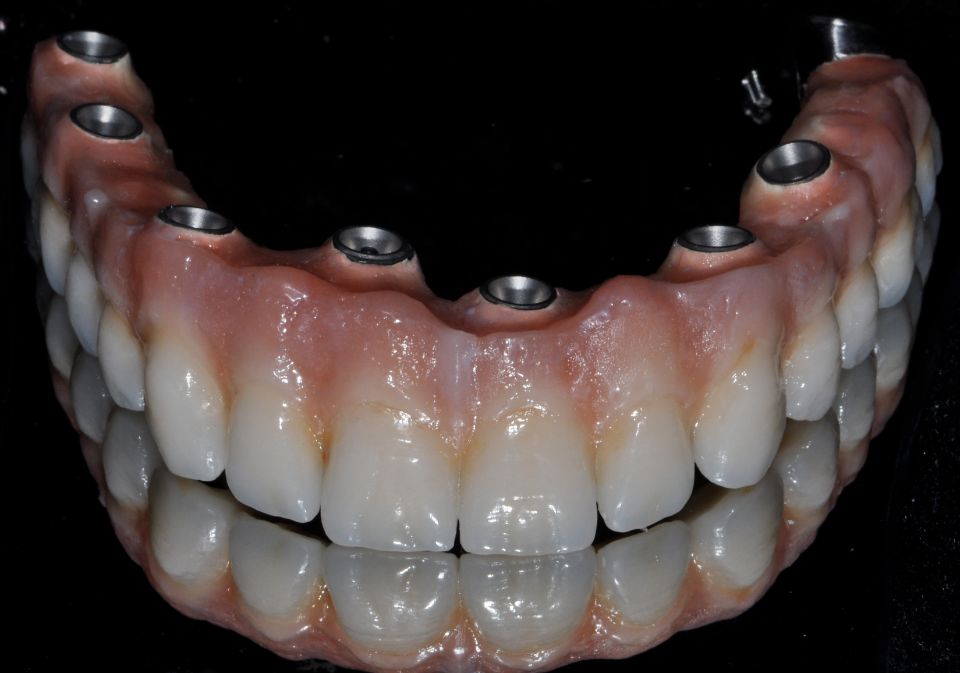

La implantologia és l´especialitat odontològica que s´ocupa de la substitució de l´arrel de la dent perduda.

La substitució es fa mitjançant una petita intervenció quirúrgica per col·locar una peça de titani dins de l'os maxil·lar.

L'implant té una rosca al seu interior on posteriorment s'enroscarà el pilar que suportarà la corona protètica.

La demora en la reposició de dents comporta alteracions funcionals i anatòmiques de l'aparell buc dental, com ara: la reabsorció de l'os maxil·lar, migracions i desplaçaments de dents romanents o alteracions fonètiques, estètiques, masticatòries, etc...

Després de la valoració de l'implantòleg i un diagnòstic molt acurat per part de l'equip professional, es plantegen diferents solucions. Depenent del problema plantejat que pot ser: pèrdua unitària, pèrdua múltiple o desdentat complet...es realitzarà la tècnica precisa per tal de millorar la qualitat de vida del pacient.

La implantologia és una de les àrees mèdiques que més ha evolucionat en els darrers anys. Això fa que la fiabilitat i la comoditat del pacient augmenti.